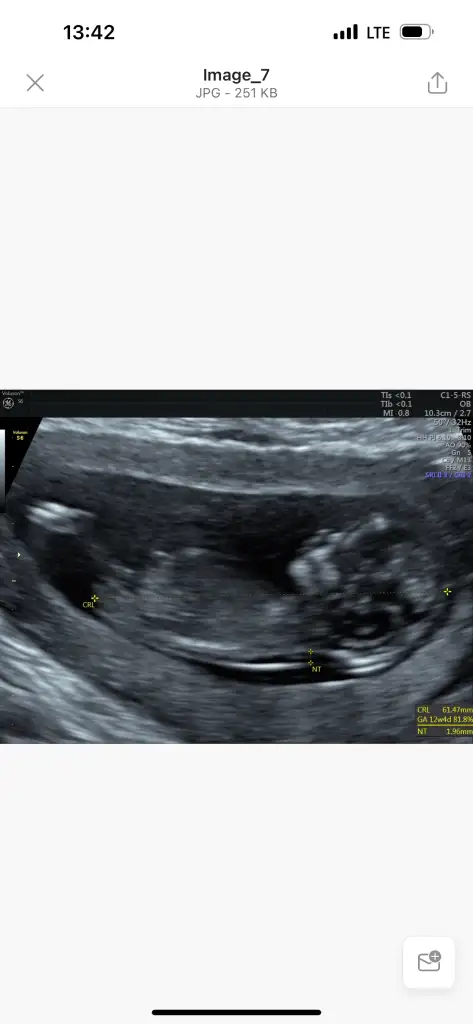

Valla forumda fetal dna da bile yanılma okudum canım down da yanılmıyormuş ama özellikle cinsiyet kromozomlarında hata çıkabiliyormuş o şekilde yanlış sonuç alıp sağlıklı doğum yapanlar var onu okuyunca şaşırdım bende, yok canım niye geç kalasın ki zaten anne karnında varsa down Allah korusun yapabilecekleri bişey yok ki tahliye edelim demek dışında, ense kalınlığı başka bir hastalığa gösterge mi bilmiyorum ama bence anne olarak yapabileceklerini yapıyorsun beklemekten başka yapacak birşey yok, hayırlı haberler alacaksın inşallah hepimiz de öyle